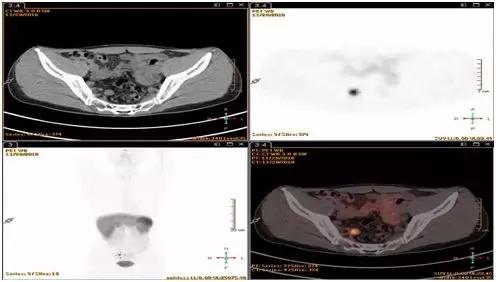

8、 直肠神经内分泌瘤需要做 68 镓-PET-CT或奥曲肽扫描么?

答:直径小于1cm,CT或MRI检查无可疑转移病灶的,可以不做;直径超过1cm,CT/MRI等影像检查有可疑结节或病灶的需要做。

9、 肠周发现几毫米的淋巴结有可能是转移么?

答:目前研究认为,直肠NET出现肠周淋巴结超过5mm,80%的可能性是转移的,因此出现这种淋巴结建议做生长抑素受体显像进一步明确。